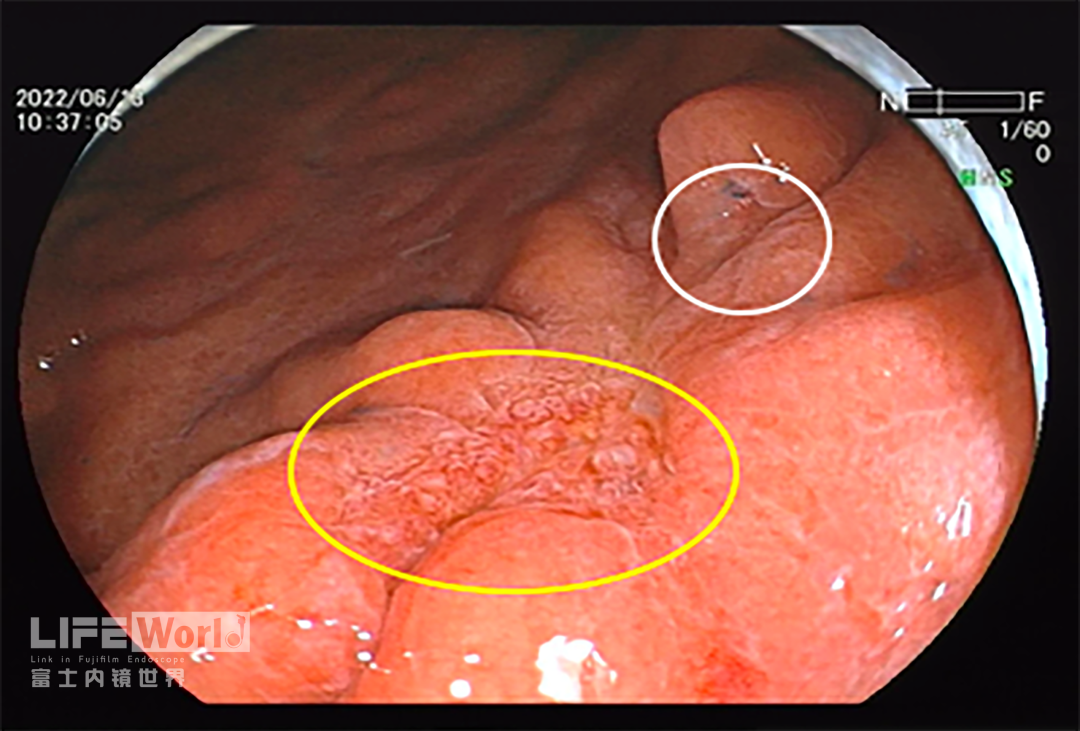

白光观察:胃体下段大弯侧可见一处中央凹陷的病变,色红,范围约1.2×0.6cm,周围黏膜集中、中断。

除了黄圈内考虑为癌灶的病变发红,白圈内考虑为上皮内瘤变的病变也略发红。

充气吸气后,可见病变凹陷处延展性欠佳,周围皱襞集中、中断。